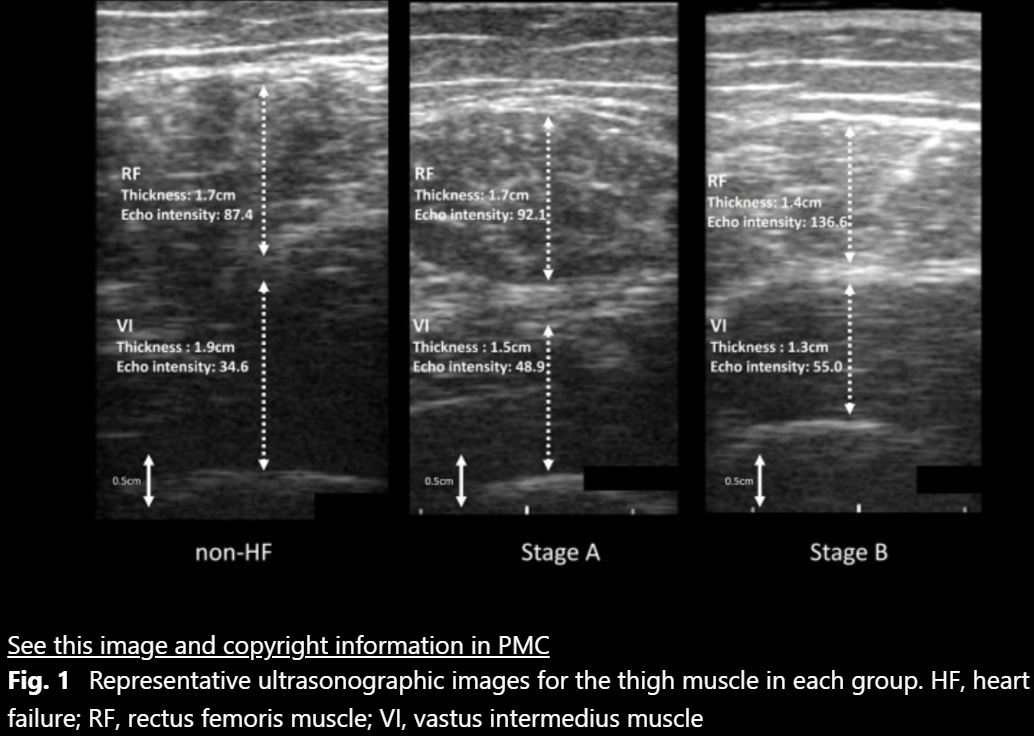

Association between heart failure in asymptomatic stages and skeletal muscle function assessed by ultrasonography in community-dwelling older adults.

Toshimi Satoh, Yosuke Kimura, Tomohiro Kakehi et al. | BMC Geriatrics 24: 871 | 2024年10月

地域在住高齢者における無症候性心不全の罹患と骨格筋機能の関係-超音波画像を用いた調査-

第8回日本栄養・嚥下理学療法研究会 セレクション演題 | 2023年3月